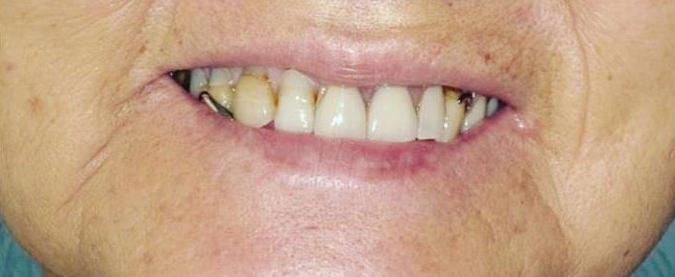

All-On-4 Dental Implants: A Reason To Smile Again

All-on-Four: One Full Arch Of Teeth, Four Dental Implants

To fully understand this remarkable technique for replacing teeth, you should first understand what a dental implant is. An implant is a small titanium screw that fits inside your jawbone and replaces the root-part of a missing tooth. Minor surgery is required to insert the implants. Once the implant is in place, a crown is attached to give you a highly realistic-looking and functional prosthetic tooth.

Here’s where it gets really interesting: You do not need a dental implant for each and every one of your missing teeth. All you need is four precisely placed implants on the top of your mouth, and four on the bottom, to restore your full smile. That’s the beauty of the all-on-four. And because the implant is made of titanium, it has the unique ability to fuse to living bone and function as part of it. So eventually, the dental implant becomes part of the jawbone and serves as a strong, long-lasting foundation for your new teeth.

Besides ensuring that your implants are permanently fixed in place, this bone fusion has another important benefit: it prevents future bone loss in the jaw. This helps to maintain a more youthful facial structure – and better oral health. But perhaps the biggest surprise about the all-on-four is how quickly it can transform your life.